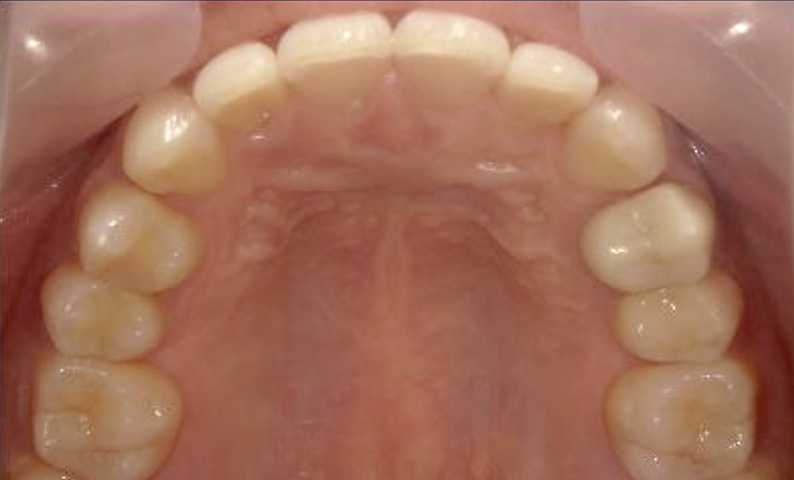

症例_025 上顎だけの部分矯正

治療期間:7ヶ月金額:30万円+税女性前歯のガタガタ上の前歯だけ